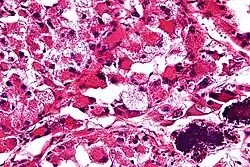

W obrazie mikroskopowym charakterystyczna jest obecność gęstego beleczkowania o zróżnicowanej grubości dzielącego utkanie guza na gniazda komórek nowotworowych. W przegrodach łącznotkankowych obecne są cienkościenne naczynia krwionośne wyłożone pojedynczą warstwą spłaszczonych komórek nabłonkowych[5]. W obrębie centrum gniazd komórek widoczna jest martwica i utrata spójności komórek (kohezja), co jest przyczyną utworzenia charakterystycznego pseudopęcherzykowego wzoru utkania[5]. Rzadziej utkanie jest bardziej lite, szczególnie u niemowląt i u dzieci, komórki są ułożone w rozproszone arkusze bez tworzenia układu gniazd i pseudopęcherzyków[12][13].

Komórki nowotworowe są duże, okrągłe lub wielokątne, wyraźnie ograniczone, wykazują pewną niewielką zmienność wielkości i kształtu. Komórki zawierają obfitą ilość eozynofilnej, rzadziej jasnej, drobnoziarnistej cytoplazmy, jedno lub dwa pęcherzykowate jądra komórkowe z jednym jąderkiem[5][12]. Atypia jądrowa jest rzadka[12]. Aktywność mitotyczna jest niewielka i liczba figur mitotycznych jest uboga[5]. Niemal stałą cechą jest inwazja naczyń krwionośnych[12][14]. Barwienie PAS ujawnia wewnątrzkomórkowy glikogen oraz kryształy w kształcie pręcików zbudowane z białka transportującego kwasy monokarboksylowe (MCT1) i CD147[5][15]. Kryształy mają znaczenie diagnostyczne, występują one w około 80% przypadków mięsaka pęcherzykowego[13].

Materiał pobrany podczas biopsji lub preparat pooperacyjny jest barwiony i oceniany pod mikroskopem. Obraz mikroskopowy mięsaka pęcherzykowego po wybarwieniu H+E jest charakterystyczny. Typową jest obecność pseudopęcherzyków, gniazd komórkowych i łącznotkankowych przegród z cienkościennymi naczyniami[7][13]. Nowotwór różnicuje się przede wszystkim z pęcherzykowym mięśniakomięsakiem prążkowanokomórkowym, przyzwojakiem i przerzutami raka nerki[8].